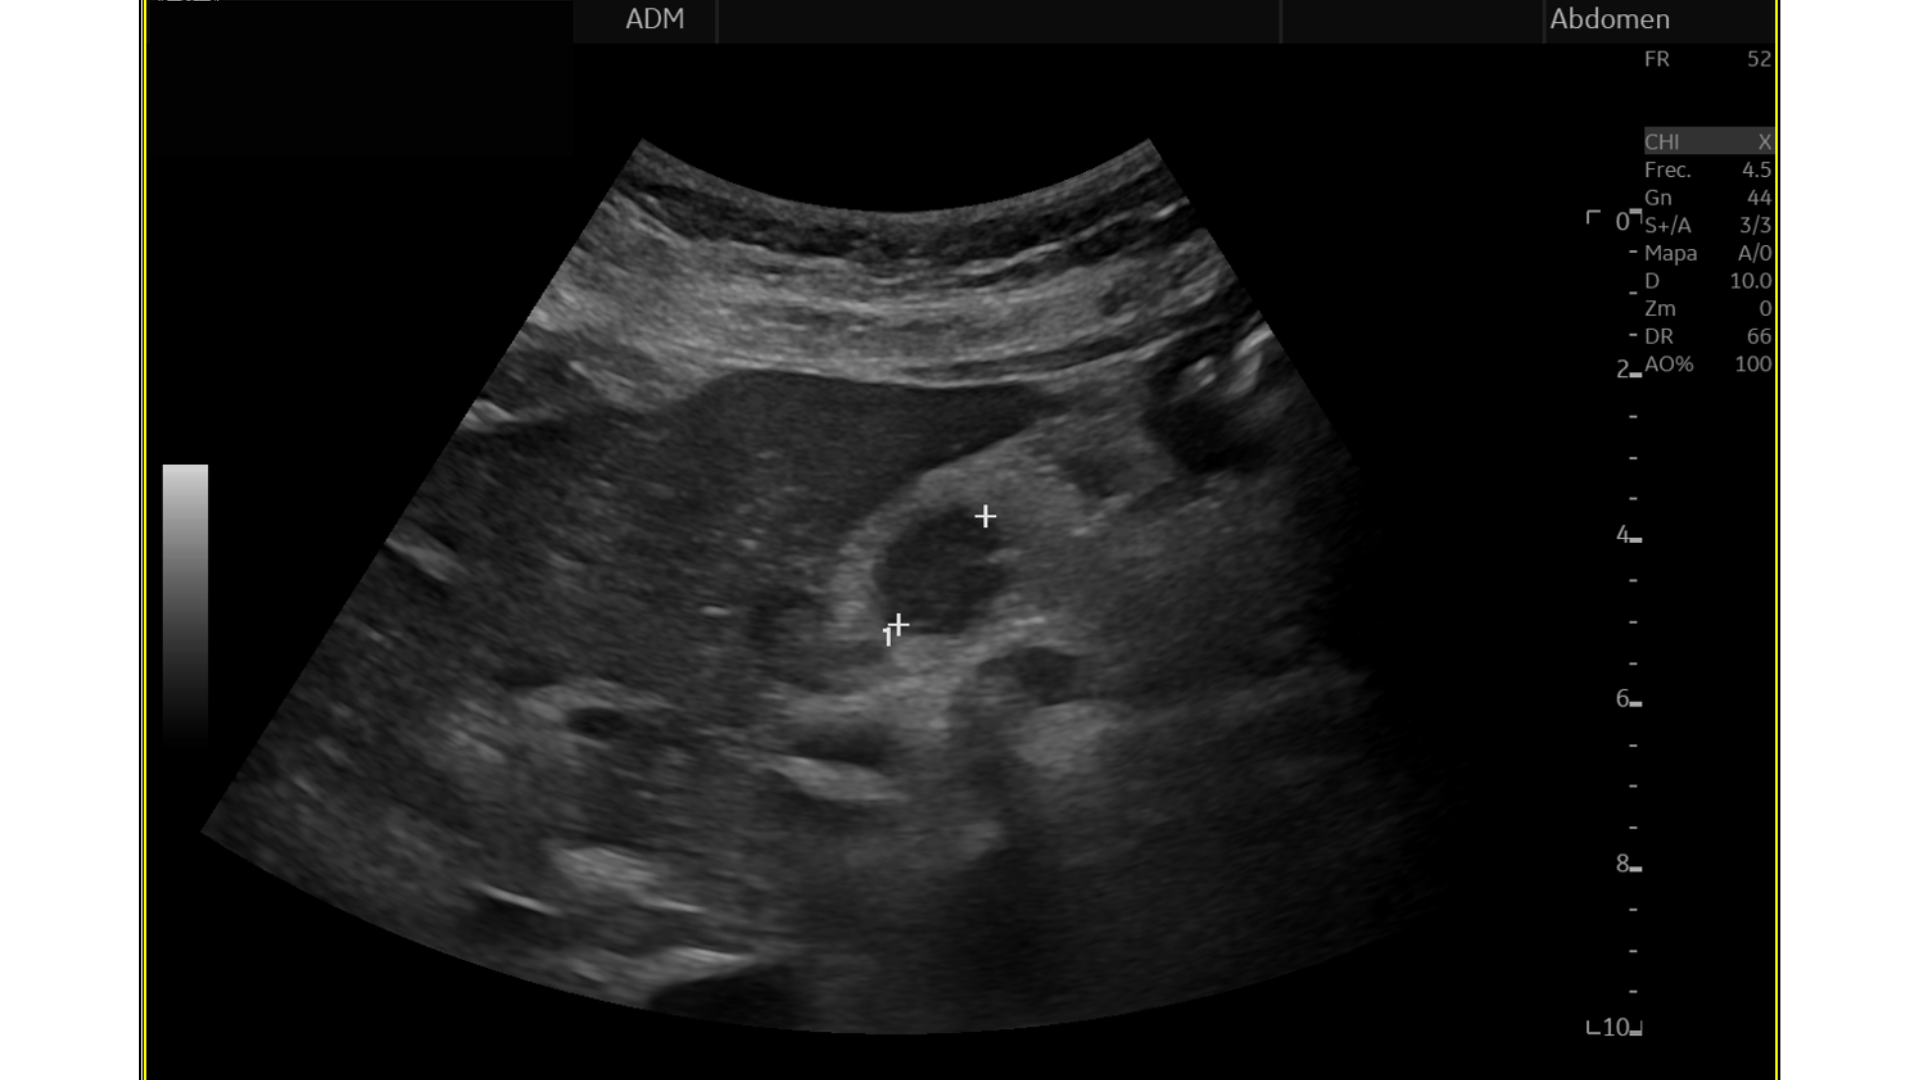

Eco Abdominal: Múltiples imágenes nodulares heterogéneas en ambos lóbulos hepáticos sugestivas de M1. Destaca imágen nodular, hipoecogénica en cabeza/cuerpo de páncreas de aprox. 17 mm, podría corresponderse con proceso neoformativo primario.